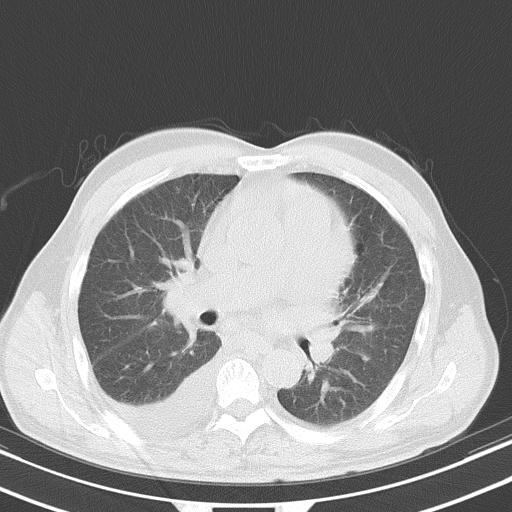

以下是引用zjzjr在2010-3-21 17:39:00的发言:[br]右下中心型肺癌并阻塞性肺炎/不张,纵膈淋巴结肿大,右侧大量胸腔积液,左侧少量胸腔积液

以下是引用zxl51642在2010-3-21 17:06:00的发言:[br]右下中心型肺癌并阻塞性肺炎/不张,纵膈淋巴结肿大,右侧大量胸腔积液,左侧少量胸腔积液,少量腹水。建议纤维支气管镜进一步检查。